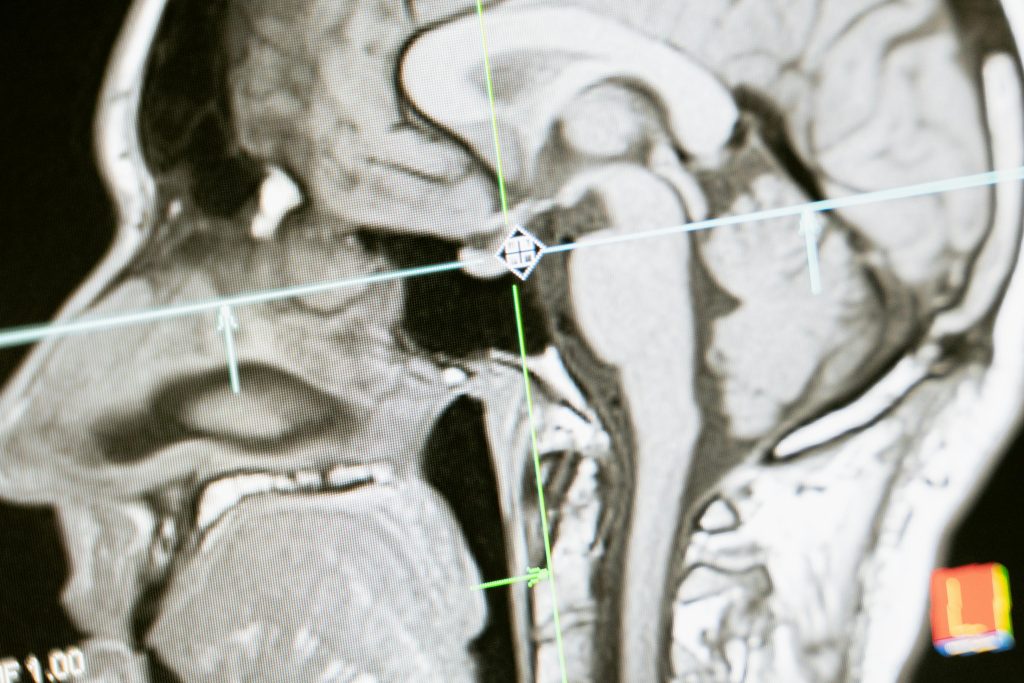

A inteligência artificial (IA) tem revolucionado diversas áreas, incluindo a medicina, onde sua capacidade de analisar grandes volumes de dados a torna uma ferramenta valiosa no diagnóstico de doenças. A IA utiliza algoritmos avançados e técnicas de aprendizado de máquina para identificar padrões em dados que seriam impossíveis de serem detectados por humanos em um tempo razoável. Essa tecnologia é particularmente eficaz em ambientes onde a quantidade de informações é massiva, como em imagens médicas, registros eletrônicos de saúde e dados genômicos. Porque a capacidade melhora a eficiência dos diagnósticos e aumenta a precisão, permitindo que os profissionais de saúde tomem decisões mais bem informadas e fundamentadas.

Estudos têm mostrado que algoritmos de IA podem detectar câncer em imagens de mamografias com uma precisão superior à de radiologistas experientes. Essa capacidade é crucial, pois diagnósticos precoces aumentam significativamente as chances de tratamento eficaz e cura, impactando diretamente a sobrevida dos pacientes. Além disso, pode ajudar a personalizar os tratamentos, prevendo como diferentes pacientes responderão a terapias específicas com base em suas características genéticas e clínicas.

Diante da atual situação, diversas instituições se mobilizam para desenvolver formas eficientes de análise, como o da detecção de câncer de mama por meio de imagens analisadas por IA, que têm mostrado resultados promissores.

Um estudo realizado pela Universidade de Stanford revelou que um sistema de IA foi capaz de detectar câncer de mama com uma taxa de precisão de 94,6%, superando a média de 88% dos radiologistas. Além disso, o exame de sangue OncoSeek, que busca detectar múltiplos tipos de câncer através da análise de biomarcadores, mostrou uma sensibilidade de 51,7% na detecção precoce de nove tipos de câncer, incluindo câncer de pulmão e cólon. Esses estudos não apenas demonstram o potencial da IA na detecção precoce de câncer, mas também destacam a importância de continuar investindo em pesquisas que explorem essa tecnologia. Lembrando sempre que a combinação de análises de imagem com dados genômicos e clínicos pode levar a uma abordagem mais holística e personalizada no tratamento do câncer.